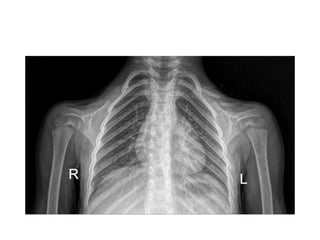

Cleidocranial dysostosis

• Disorder in which the bones formed by

intramembranous ossification (primarily the

clavicles,cranium, and pelvis) are abnormal

• Autosomal dominant

• Chromosome 6

• Identified within the first 2 years of life

• most common defect is U/L or B/L loss of the

lateral end of the clavicle, with failure of

development of the middle third of the

clavicle second in frequency

• second metacarpal is unusually long

enlarged cranium,

widened sutures, and

a persistent anterior fontanel

symphysis pubis is widened and vertical hypoplastic iliac wing

CLEIDOCRANIAL DYSPLASIA.

short, horizontally running rib with widening of

the costochondral connections.